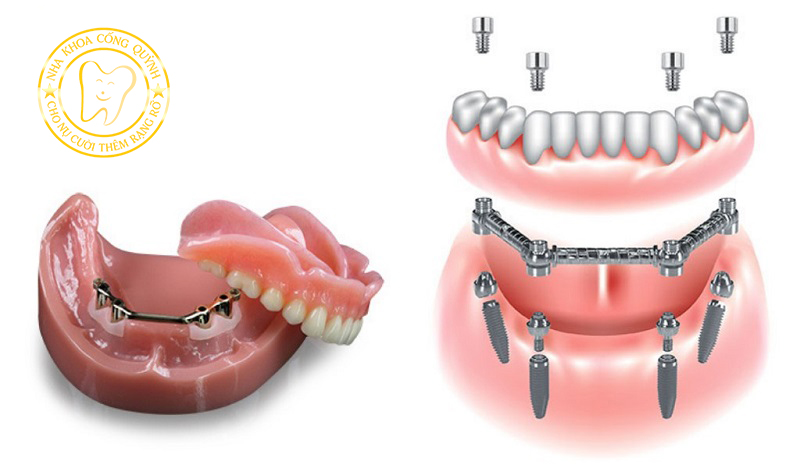

Đối với người mất răng toàn hàm, hiện nay có hai giải pháp phục hình phổ biến.

• Hàm giả tháo lắp

• Cấy ghép Implant toàn hàm

Mỗi phương pháp đều có những ưu điểm và hạn chế riêng.

Hàm tháo lắp là phương pháp truyền thống, thường được sử dụng cho người mất nhiều răng hoặc mất răng toàn hàm.

Ưu điểm của phương pháp này là chi phí thấp và thời gian thực hiện nhanh. Tuy nhiên, nhiều người gặp một số bất tiện trong quá trình sử dụng.

Cấy ghép Implant giúp thay thế chân răng đã mất bằng trụ Implant đặt vào xương hàm, sau đó phục hình răng giả bên trên.

Phương pháp này mang lại khả năng ăn nhai ổn định hơn và giúp duy trì cấu trúc xương hàm.

Trong các kỹ thuật Implant toàn hàm, All-on-4 là một giải pháp được nhiều bác sĩ lựa chọn cho người mất răng toàn hàm.

Implant All-on-4 được nhiều bác sĩ lựa chọn vì mang lại nhiều lợi ích trong phục hồi răng toàn hàm.

• Số lượng trụ Implant ít hơn so với phương pháp truyền thống

• Giảm nhu cầu ghép xương trong nhiều trường hợp

• Phục hồi khả năng ăn nhai ổn định

• Hàm răng cố định chắc chắn hơn so với hàm tháo lắp

Đối với người mất răng lâu năm, All-on-4 giúp cải thiện chức năng ăn nhai và mang lại cảm giác gần giống răng thật.